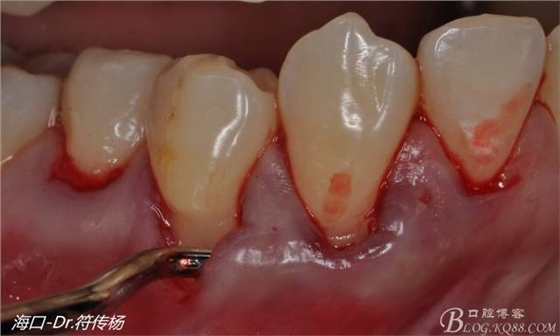

最后使用牙齦乳頭分離器分離牙齦乳頭